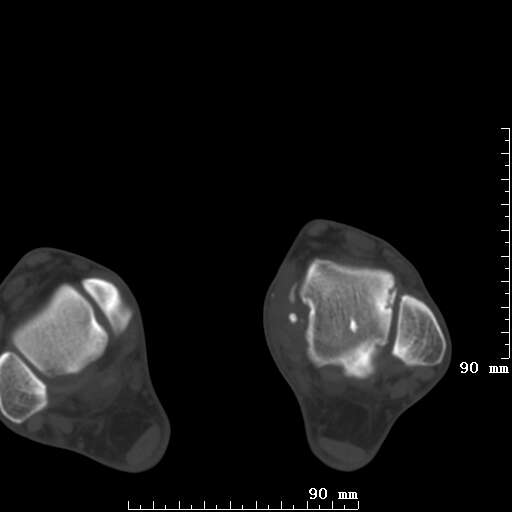

标题: CT19820:外伤一天,如何定性.男27Y [打印本页]

标题: CT19820:外伤一天,如何定性.男27Y

排除下创伤性关节炎吧,距骨有些囊变和硬化,周围韧带软组织有些机化、钙化。不是很像距骨无菌性坏死,感觉在关节面上的多,而不是距骨里面。

未见骨折及脱位像。距骨像是剥脱性软骨炎

支持!(踝关节距骨表面囊变和硬化 缺损)

距骨剥脱性软骨炎可能;踝关节创伤性关节炎?

未见明确新鲜骨折改变,距骨剥脱性软骨炎或踝关节创伤性关节炎可能。